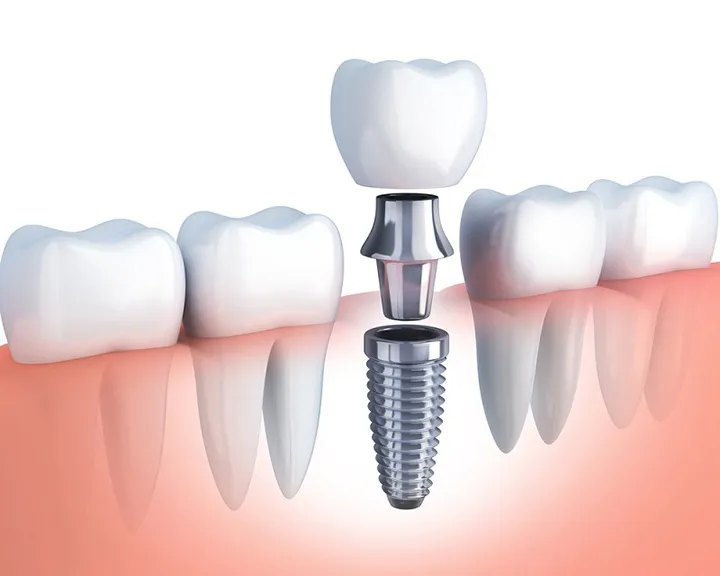

Implant là 1 loại vít nhỏ có kích thước vừa bằng 1 chân răng thật. Bộ phận này được làm từ Titanium có khả năng tương thích sinh học khá tốt với xương. Kỹ thuật cấy ghép răng Implant là kỹ thuật trồng răng giả phổ biến. Nó được thực hiện bằng cách cấy ghép 1 chân răng giả làm bằng Titanium vào trong xương hàm ở vị trí răng đã mất. Từ đó, nó giúp tạo ra các chân răng nhân tạo. Sau đó gắn răng giả lên đó với mục đích thay thế răng đã bị mất.

- Kỹ thuật cấy ghép implant phục hình răng mất một cách toàn diện từ chân răng đến thân răng. Kỹ thuật này sẽ thực hiện giống như cấu tạo của một chiếc răng thật. Đây là điểm đặc biệt mà chưa có phương pháp nào khác có thể làm được.

- Trước đây, phương pháp cầu răng sứ phải mài 2 răng cạnh răng mất làm trụ nâng đỡ. Với phương pháp cấy ghép implant hoàn toàn khắc phục được điều này. Implant không hề tác động đến bất kỳ chiếc răng nào và chỉ thực hiện tại vị trí mất răng. Từ đó bảo tồn nguyên vẹn các răng bên cạnh.